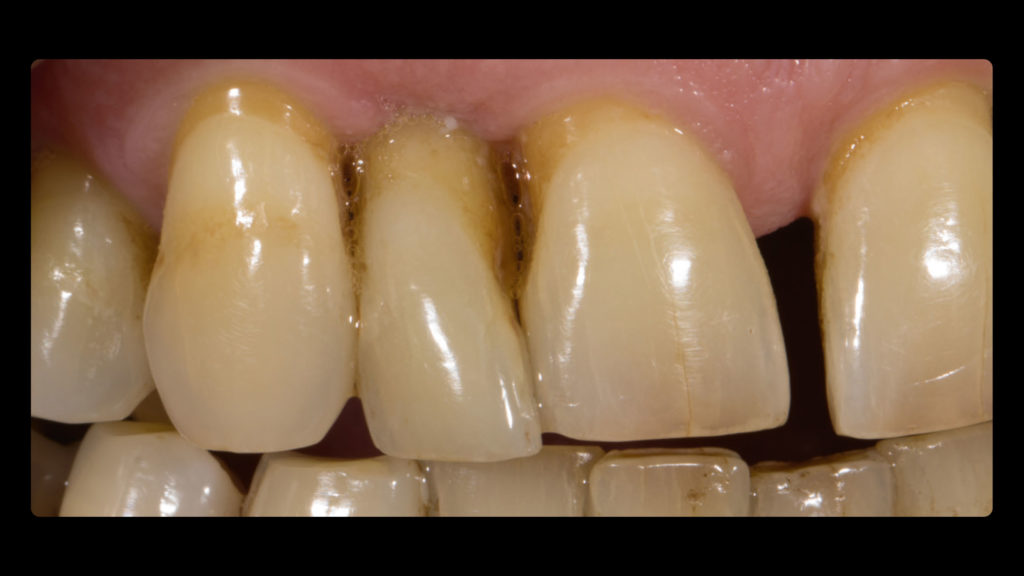

Auf Wunsch des Patienten sollte der zu rekonstruierende laterale Schneidezahn die Charakteristika des mittleren Inzisiven 21, also seines direkten Nachbarzahns aufweisen. Normalerweise hätte man sich an dem noch verbliebenen lateralen Schneidezahn im ersten Quadranten orientiert, doch leider war auch dessen Zustand nicht ideal, sodass auch dieser in Bälde rekonstruiert werden sollte (Abb. 7a und b). Bei der eingehenden Betrachtung des Zahns 21 stellten wir zwar eine gewisse Ähnlichkeit mit den vom Zahnarzt gewählten Farbmusterzähnen fest, erkannten aber auch relevante Unterschiede. Aus diesem Grund starteten wir die laborseitige Analyse mit polarisierten Aufnahmen (Abb. 8a und b). Da der Patient 49 Jahre alt war, suchten wir gezielt nach charakteristischen Merkmalen natürlicher älterer Zähne und und wurden auch fündig.

- Durch Abrasion und Attrition wird die Oberfläche inzisal abgeschmirgelt. Zusätzlich entstehen Mikrorisse, aber auch Vertiefungen (Abb. 9b und c), in denen sich Verfärbungen ablagern und Konkremente anlagern – es entstehen charakteristische Verfärbungen. Und auch in den interproximalen Bereichen treten Verfärbungen stärker hervor, da sie sich schwieriger reinigen lassen.